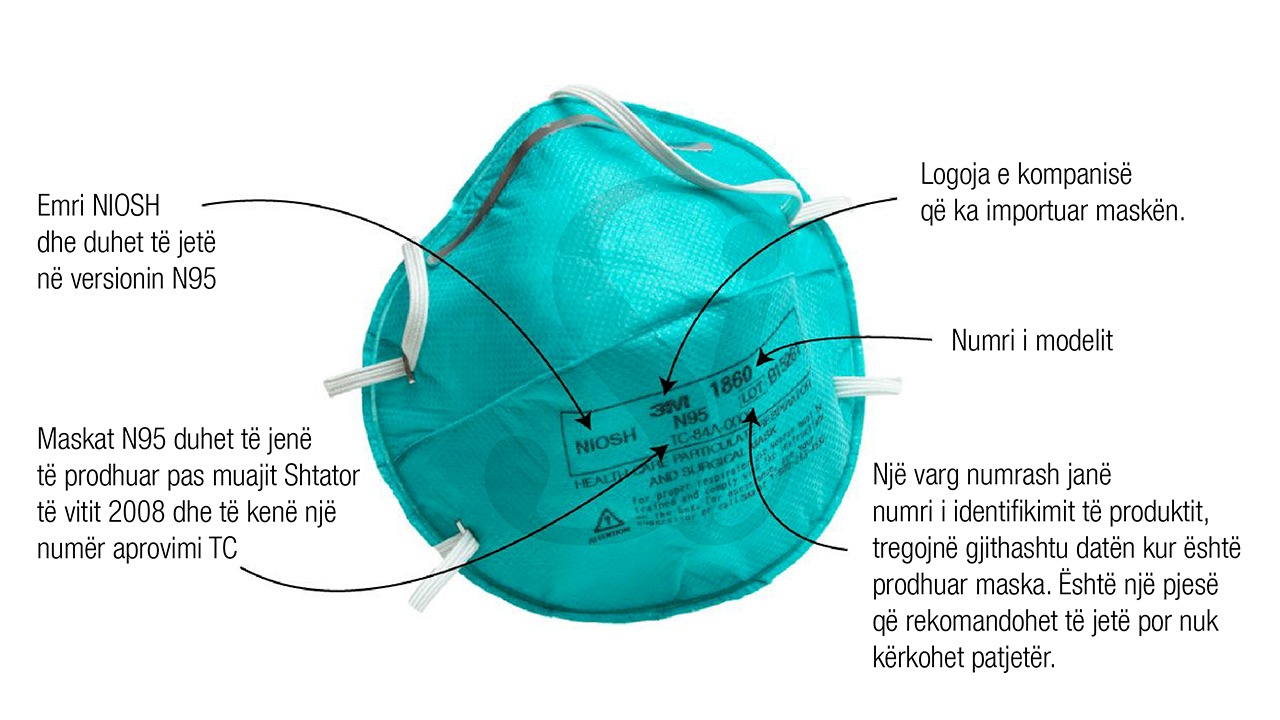

Maska N95 filtrojnë të paktën 95% të grimcave shumë të vogla kur vishen siç duhet, përfshirë spërklat që mbajnë viruse. Versione me një valvul plastike në qendër, e cila e bën maskën më të lehtë për tu npërdorur, janë të destinuara për punëtorët industrialë dhe ofrojnë mbrojtje vetëm për përdoruesit.

N95 të vërteta nuk janë të lehta për t’u mbajtur siç duhet. Ata duhet të kenë një vulë të ngushtë në fytyrë për të siguruar që i gjithë ajri të kalojë nëpër filtër në vend të skajeve. Por ata ofrojnë mbrojtjen më të mirë kundër koronavirusit, për këtë arsye OBSH ka rekomanduar që këto maska të rezervohen vetëm për punonjësit e kujdesit shëndetësor.